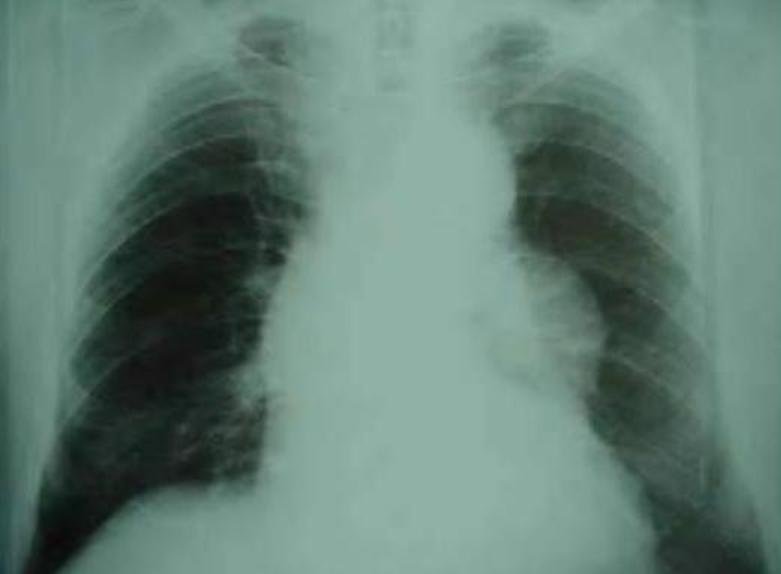

Cardiopatia congênita (provavelmente tetralogia Fallot)

Vamos analisar: temos desnutrição, baqueteamento digital, poliglobulia maciça, sopro sistólico e arco aórtico á direita. São sinais patognomônicos para hipoxia cronica causada por algum defeito cardíaco. Cardiopatias congênitas são anomalias do aparelho circulatório presentes desde o nascimento, sendo divididas em cianóticas e acianóticas. A Tetralogia de Fallot é a cardiopatia cianótica mais comum, caracterizada por comunicação interventricular, estenose subpulmonar, origem biventricular da valva aórtica e hipertrofia ventricular direita. O diagnóstico costuma ser realizado no primeiro ano de vida devido às manifestações clínicas precoces, na maioria dos casos. Contudo, em alguns casos, a associação de outras malformações cardíacas e falhas no sistema de saúde podem contribuir para realização de diagnósticos tardios, aumentando a probabilidade de prognósticos desfavoráveis.